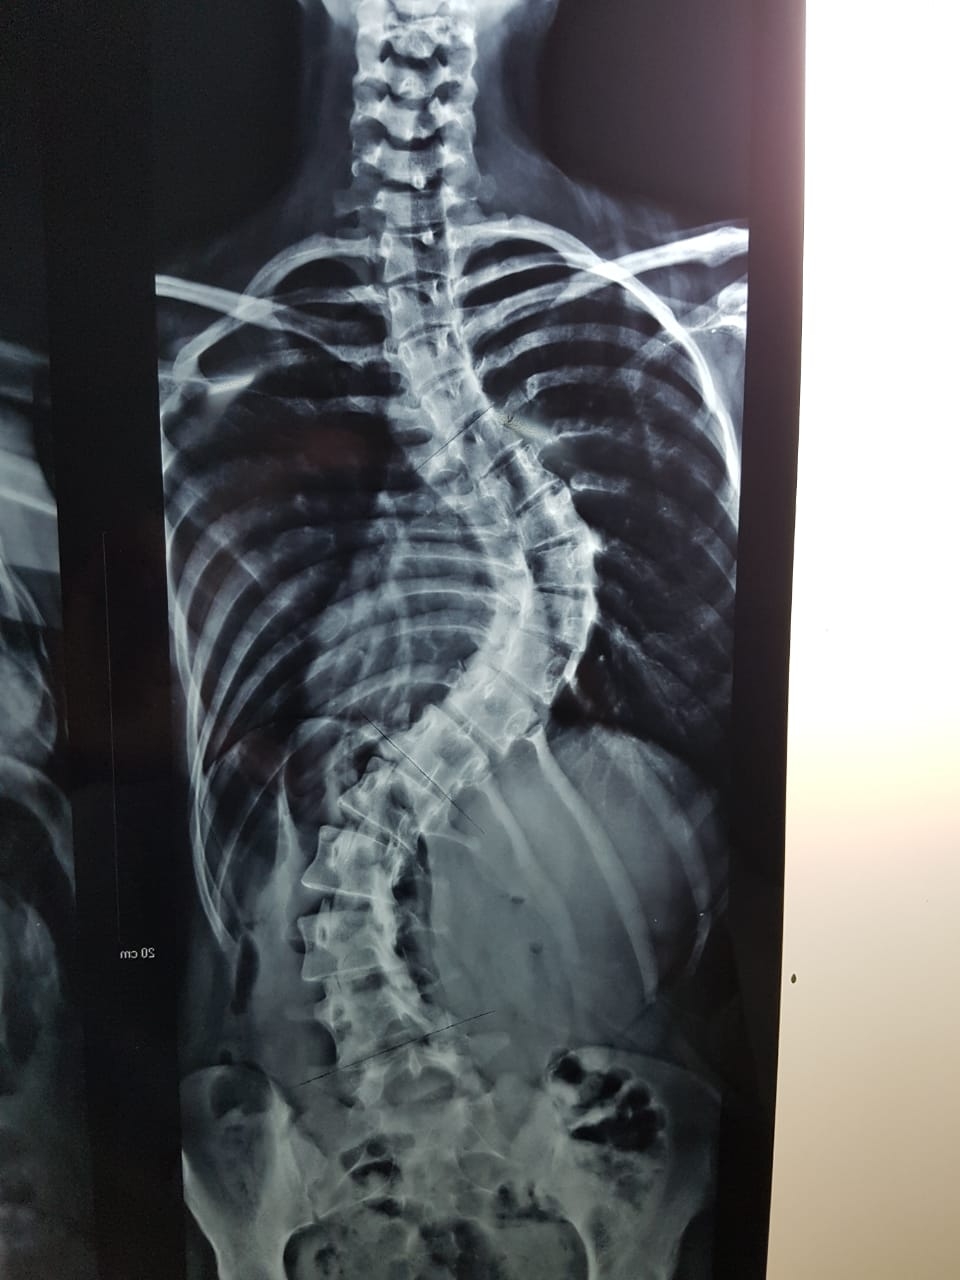

Durante el procedimiento realizaron la reducción de la desviación y fijación sobre un 80 por ciento de la columna vertebral –lumbar y dorsal-.

Tal como lo relatan los profesionales, esta clase de intervenciones se realizan, usualmente y a menor riesgo, en pacientes de edad temprana, antes que la malformación se agudice y los huesos ganen cierta rigidez. Sin embargo, en este caso, la paciente ya tenía 20 años de edad y una deformidad descompensada en su columna.

Nicolás Flores Kanter, médico que participó de la cirugía, explicó que “la intervención en sí misma llevó cinco horas en quirófano, fue compleja porque implicaba mucha pérdida de sangre; pero la paciente despertó bien y estuvo internada en sala durante 5 días, que era el objetivo del equipo de tratamiento. Ahora volvió para controles y se encuentra en perfectas condiciones, sin dolores, ni complicaciones, solo vino para que se le quitaran los puntos”.